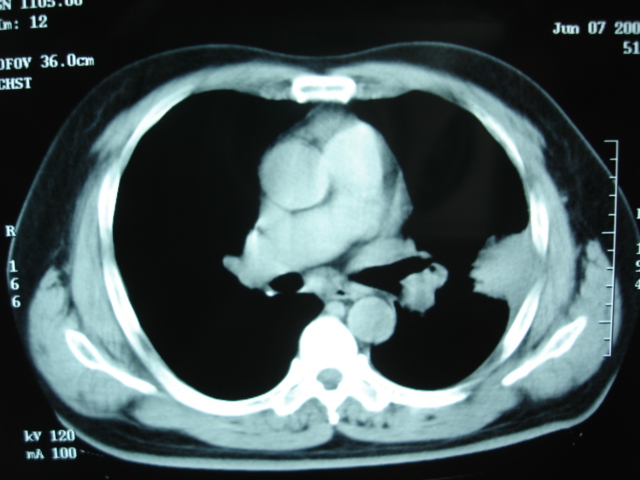

第三次ct2009.8.21

炎症,最厚一次已吸收

考虑左肺上叶炎症感染(炎性假瘤可能)。

考虑左肺上叶炎症感染,以炎性假瘤可能性大。